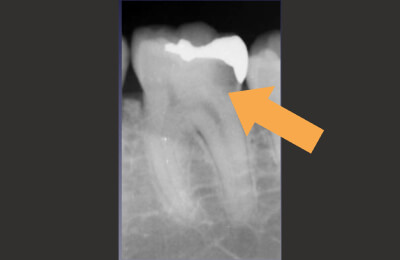

術前

-

矢印部に大きな骨吸収像

治療中

矢印部が処置されていない

根管を清掃した後

術後

骨の再生が見られる

| 主訴 | 噛むと違和感がある。 レントゲンで根の先に黒い影を指摘された。 |

|---|---|

| 治療期間 | 根管治療3回 補綴治療3回 |

| 治療費 |

(ファイバーコア・ジルコニアクラウン) |

| 治療内容 |

通法の根管治療を行いました。ラバーダム防湿、 マイクロスコープ下で未処置であった根管を発見し処置。 |

| 治療のリスク |

治療直後は反応性に一時的な腫れや痛みが出る可能性があります。 根管治療で改善が見られない場合は外科的根管治療が必要になる場合があります。 |